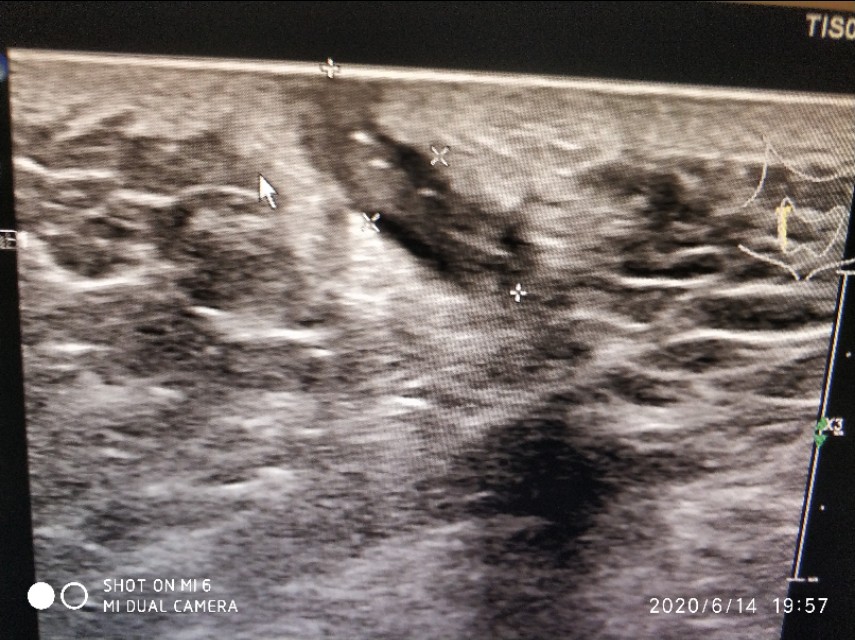

这是一个藏毛疾病的患者,不过这是一例手术后复发的病人,长得像一个小尾巴一样,里面可以见条状的线状稍高回声。我在丁香园里特别找了几幅手术中的照片,非常的难以入目,真的是少儿不宜。治疗方法一般是切开引流,还有切开一个菱形的口子,把里面一些坏死的组织挖出来。

这是我们科长做的,可以看到包块周围血流还是挺丰富的,提示可能有肉芽组织增生,里面有几根条带状的毛发回声。